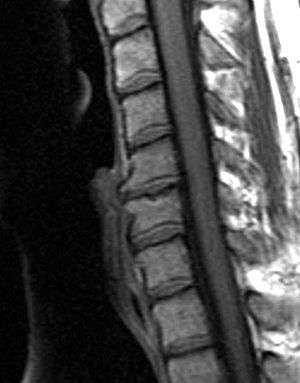

Degenerative disc disease (DDD) is breakdown of an intervertebral disc of the spine. It may cause acute or chronic low back or neck pain. The typical radiographic findings in DDD are black discs, disc space narrowing, vacuum disc, end plate sclerosis, and osteophyte formation.[1] DDD can greatly affect quality of life. Disc degeneration is a disease of micro/macro trauma and of aging, and though for most people is not a problem, in certain individuals a degenerated disc can cause severe chronic pain if left untreated.